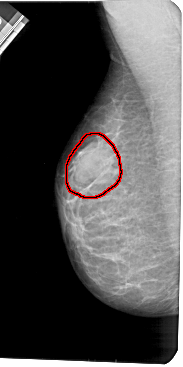

A_1419_1.LEFT_CC

LEFT_CC LINES 5266 PIXELS_PER_LINE 2671 BITS_PER_PIXEL 12 RESOLUTION 43.5 OVERLAY

FILE: A_1419_1.LEFT_CC.OVERLAY

TOTAL_ABNORMALITIES 1

ABNORMALITY 1

LESION_TYPE MASS SHAPE OVAL MARGINS OBSCURED

ASSESSMENT 4

SUBTLETY 4

PATHOLOGY BENIGN

TOTAL_OUTLINES 1

BOUNDARY